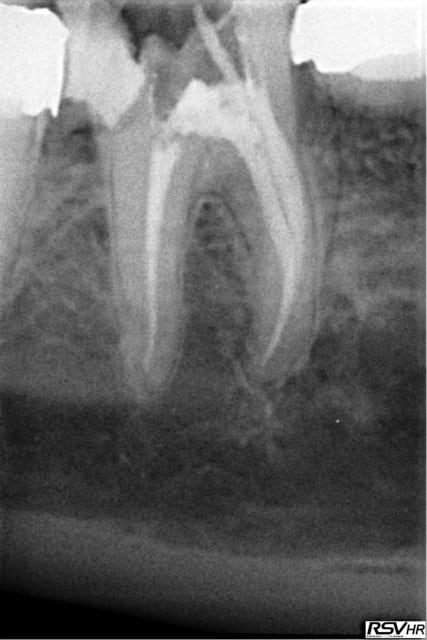

pour répondre à la question initiale du post, un cas de molaire dépulpée non couronnée.

Mise en place d'un cvimar (fuji II lc) en recouvrement de l'entrée canalaire puis onlay Empress collé.

Patiente de 21 ans.